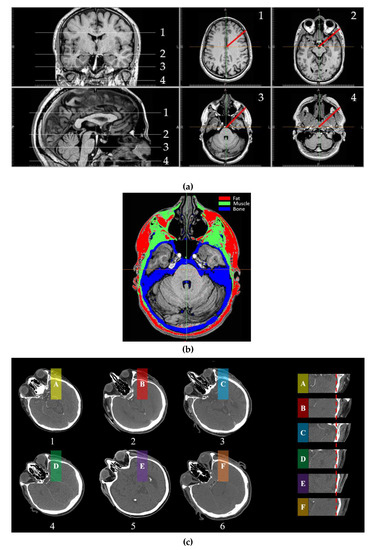

| 1 | 2 | 3 | 4 | ||||

|---|---|---|---|---|---|---|---|

| Tissue | Thickness (cm) | Tissue | Thickness (cm) | Tissue | Thickness (cm) | Tissue | Thickness (cm) |

| Brain | 8.81 | Brain | 7.37 | Brain | 1.37 | Muscle | 3.18 |

| Bone | 0.46 | Bone | 0.57 | Bone | 1.46 | Bone | 0.48 |

| Muscle | 0.31 | Muscle | 1.71 | Brain | 4.5 | Muscle | 3.56 |

| Fat | 0.78 | Fat | 0.75 | Bone | 0.66 | Bone | 0.58 |

| Skin | 0.27 | Skin | 0.31 | Muscle | 0.69 | Muscle | 0.46 |

| - | - | - | - | Fat | 0.76 | Fat | 0.52 |

| - | - | - | - | Skin | 0.36 | Skin | 0.4 |